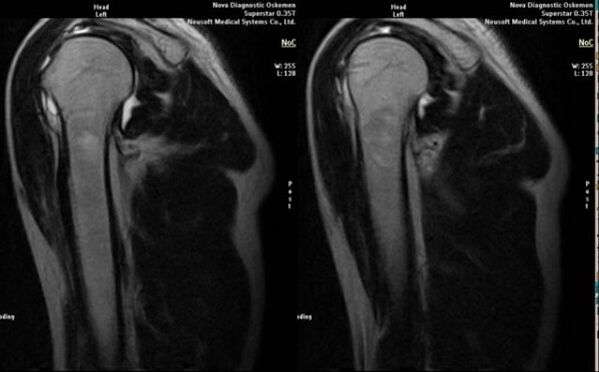

- magnetic resonance and computed tomography;

Signs directly indicating the development of arthrosis include the appearance of a significant narrowing of the joint gap, sclerosis of subcartilaginous structures, thinning of the chondrocyte layer itself, the appearance of osteophytes and the deposition of salt crystals in the intra-articular fluid.